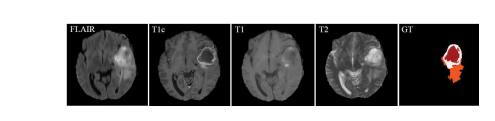

脑肿瘤的早期诊断对于临床评估和治疗规划至关重要。核磁共振成像(MRI)是一种广泛使用的成像技术,用于评估脑肿瘤,因为它提供了良好的软组织对比度而无需辐射。常用的序列包括T1加权、增强T1加权(T1c)、T2加权和液体衰减反转恢复(FLAIR)图像。不同的序列可以提供互补信息,用于分析胶质瘤的不同亚区。例如,T2和FLAIR突出了具有肿瘤周围水肿的肿瘤,被称为整个肿瘤。T1和T1c突出了没有肿瘤周围水肿的肿瘤核心,被称为肿瘤核心。在T1c中还可以观察到肿瘤核心的增强区域,具有高信号强度,被称为增强肿瘤核心。在这项工作中,我们将不同序列的这些图像称为模态。因此,应用多模态图像可以减少信息不确定性,并提高临床诊断和分割准确性。图1展示了四种MRI模态和相关的地面真实情况,我们可以看到FLAIR可以提供关于整个肿瘤的重要信息,而T1c可以提供关于肿瘤核心的更多信息(包括增强肿瘤和Net&Ncr区域)。

Fig. 1. Example of data from a training subject. The first four imagesfrom left to right show the MRI modalities: Fluid attenuation inversionrecovery (FLAIR), contrast enhanced T1-weighted (T1c), T1-weighted (T1),T2-weighted (T2) images, and the fifth image is the ground truth labels,Net&Ncr is shown in red, edema in orange and enhancing tumor in white,Net refers non-enhancing tumor and Ncr necrotic tumor.

图1. 训练对象数据示例。从左到右的前四幅图像显示了MRI模态:液体衰减反转恢复(FLAIR)、增强T1加权(T1c)、T1加权(T1)、T2加权(T2)图像,第五幅图像是地面真实标签,Net&Ncr以红色显示,水肿以橙色显示,增强肿瘤以白色显示,Net代表非增强肿瘤,Ncr代表坏死性肿瘤。